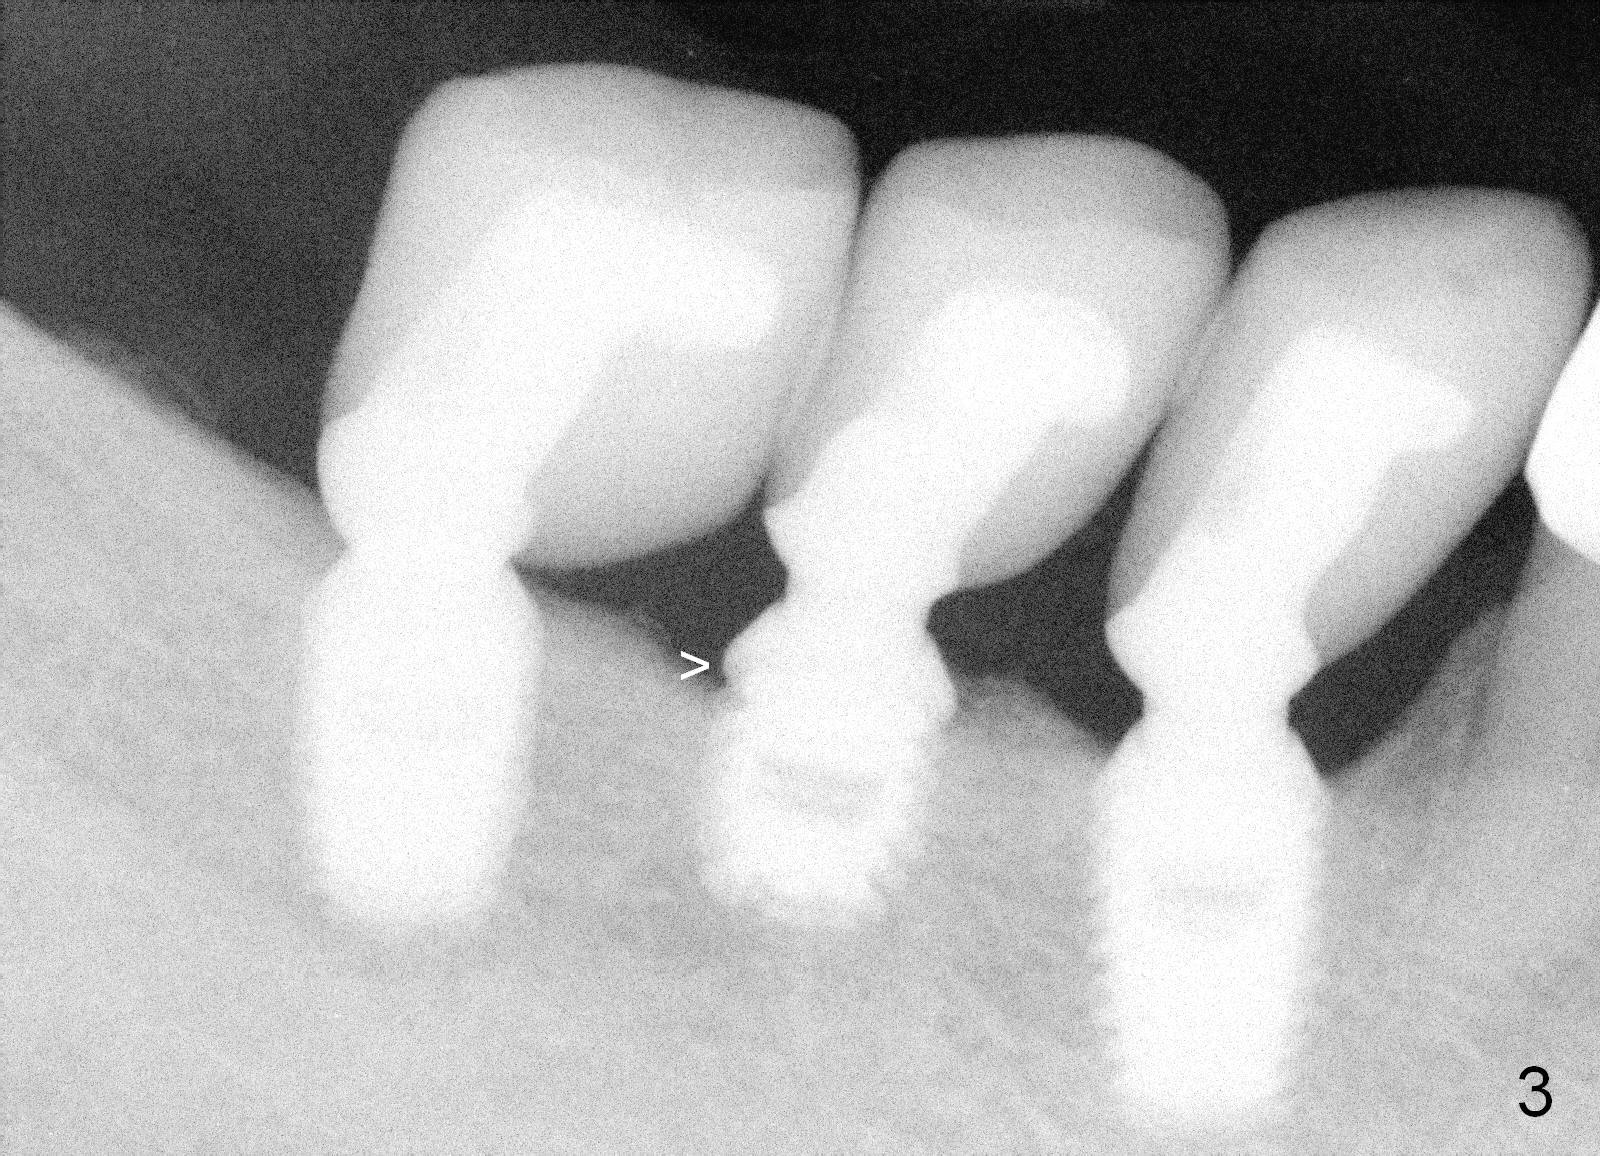

A 48-year-old man had 3 implants placed at #28-30 nearly 10 years ago (Fig.1). The implant at #29 is 4.5x6 mm because of proximity to the Mental Foramen. Bone shows gradual resorption around the implant at #29 two and 5 years postop (Fig. 2,3 >). It became loose when he accidentally bit on a piece of bone (Fig.4). A 4.5x11 (Fig.4) or 14 (Fig.2) mm tissue-level implant will be placed after Metronidazole treatment. CT will be taken tomorrow before surgery to further confirm the bone height. Since the previous implant was placed distally, the new one should be placed more mesially.